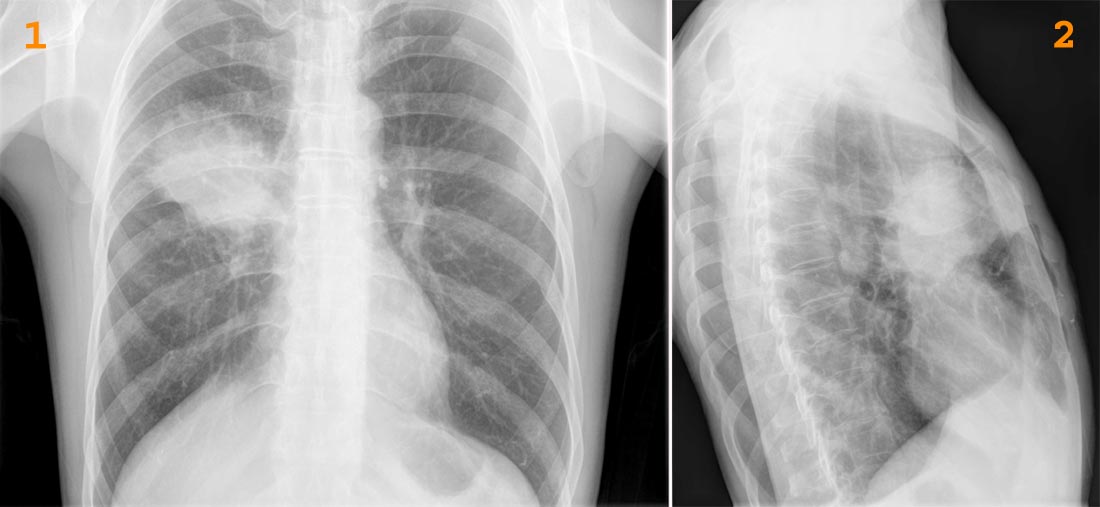

Рентгеновские снимки опухоли Панкоста